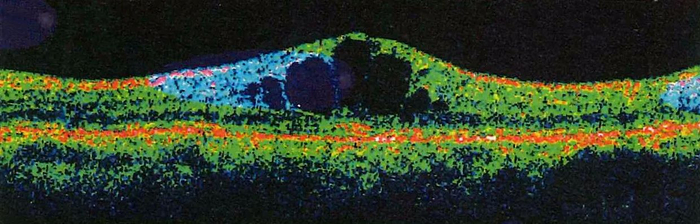

图3:光学相干断层扫描:黄斑区明显水肿、隆起

据统计,深圳市20岁及以上糖尿病患者数目前已达53万,有4成人仍不知自己得了糖尿病。根据国际糖尿病联盟的数据,糖尿病人中约有15%的被发现患有黄斑水肿,即深圳的糖尿病性黄斑水肿约有8万人,若不及时治疗,25%的人将在三年内出现严重视力下降。

深圳希玛林顺潮眼科医院院长、国际名医林顺潮介绍,糖尿病引发的视网膜病变并未得到重视。糖尿病视网膜病变初期通常都是无声无息、没有明显病征。如果一旦出现视力模糊等症状时,应立刻求医及早接受合适治疗。林顺潮举例,曾接诊过一名40岁的患者,患高血压、糖尿病6年多,因视力下降前来就诊,被诊断为“双眼糖尿病性视网膜病变”,当时建议应及时采取双眼激光治疗,但患者并未采纳医生建议。一年后视力持续变差前来就诊,此时双眼晶体混浊、右眼视力0.1,左眼视力仅可看见手指数,经过详细的检查,此时已病变严重,出现牵拉性视网膜脱离和玻璃体积血、黄斑囊样水肿等多发病变。